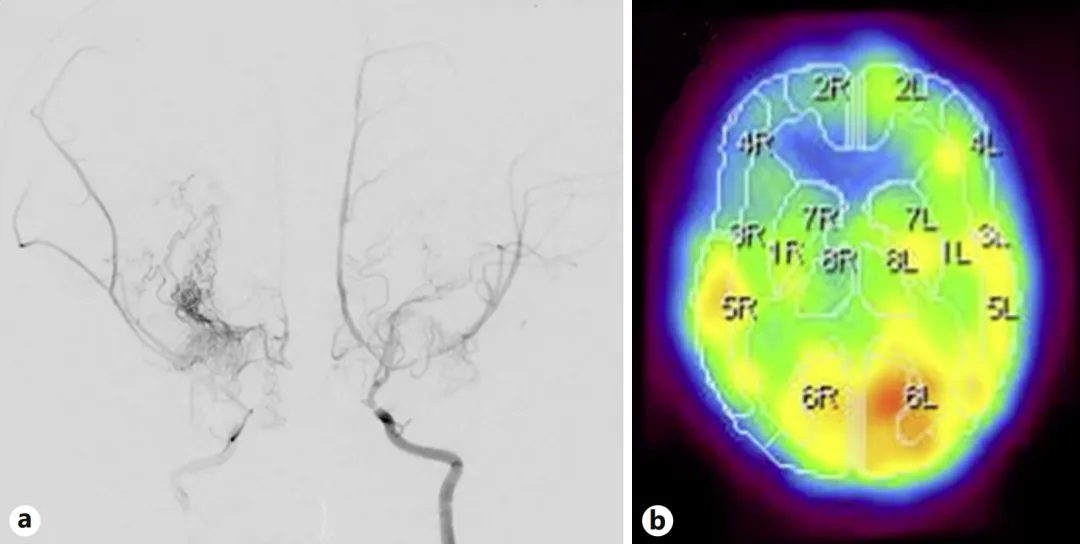

数字减影血管造影(DSA)显示双侧颈内动脉末端、大脑前动脉近端及大脑中动脉严重狭窄。(如图a,就像三条主干道同时堵车,脑组织正在“缺氧”的边缘挣扎。)

123I-IMP SPECT显示右侧额叶的脑血流已经显著减少,正是这里发生过脑梗死(如图b,这解释了她反复猝倒的原因:大脑缺血时,身体会突然失去力量。)